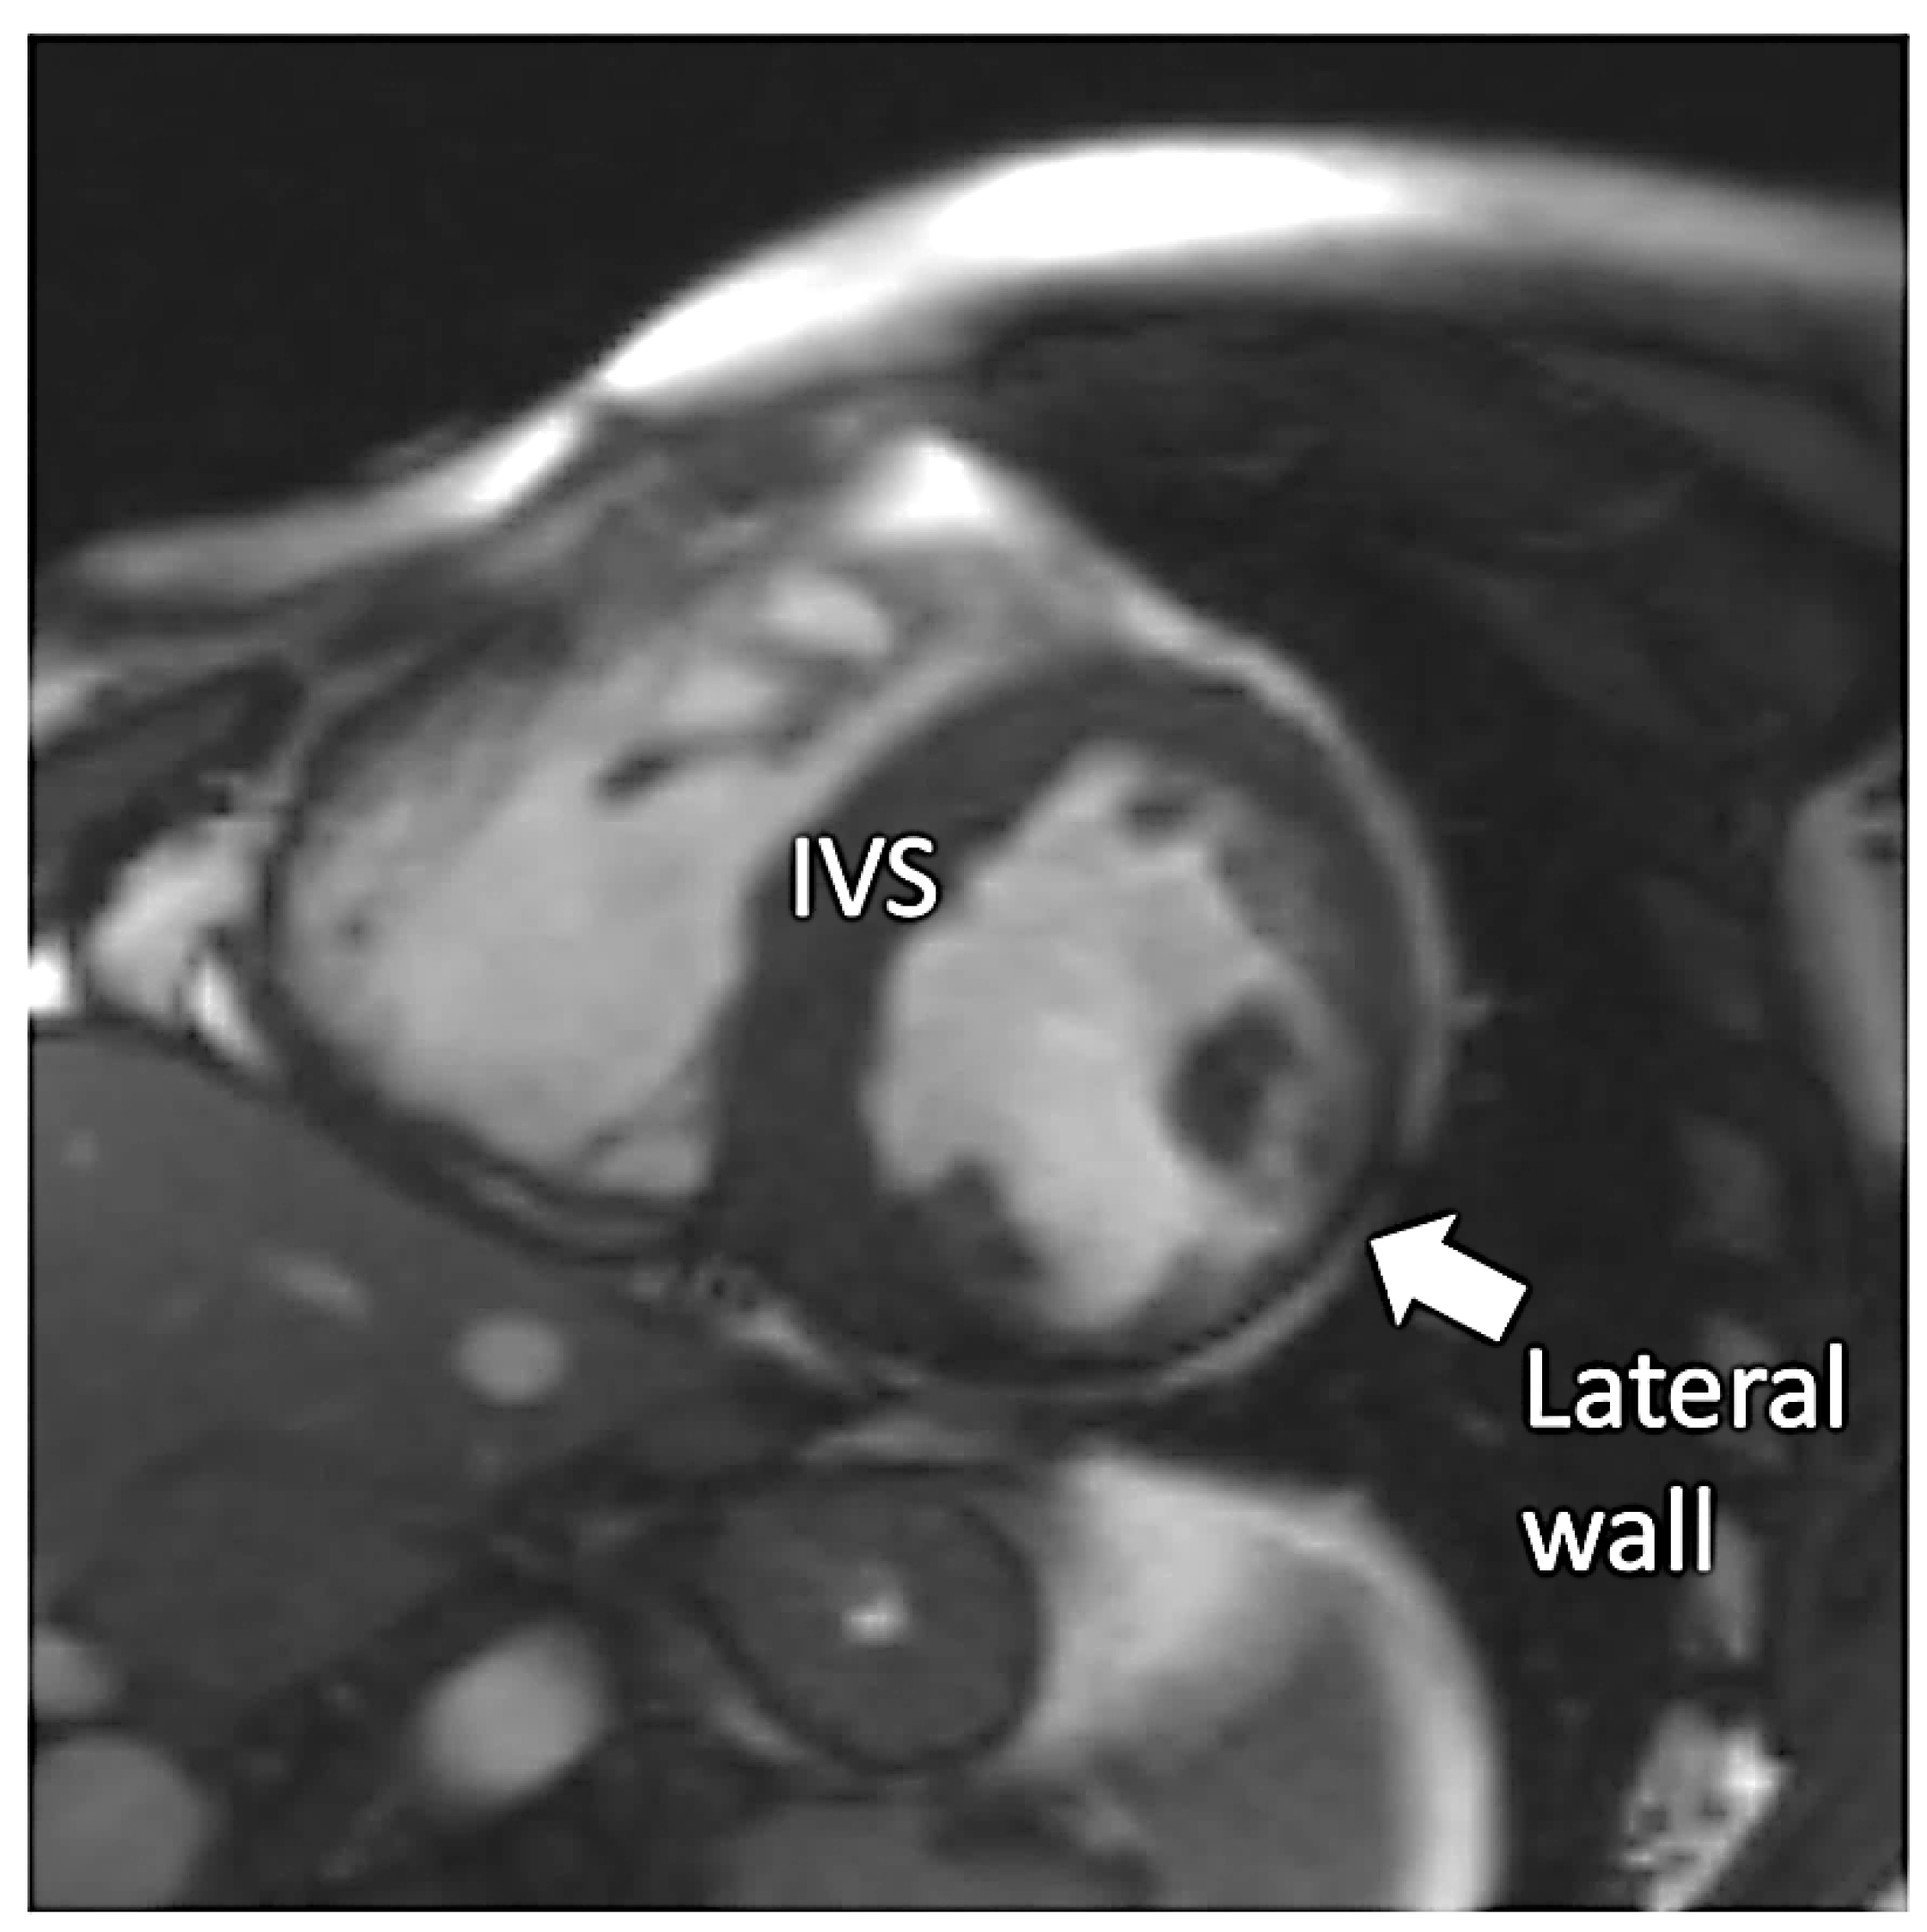

Figure 3.

Steady-state free precession short axis view demonstrating increased thickness of the interventricular septum (IVS) and thinning of the left ventricular lateral wall (arrow).